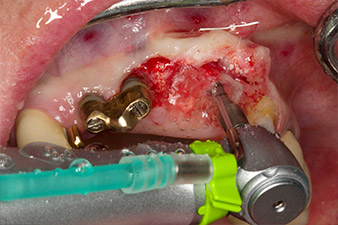

le forage pilote est effectué avec le nouvel Implantmed et le contre-angle WS-56 L

Fig. 2 : Deux mois plus tard, le forage pilote est effectué avec le nouvel Implantmed et le contre-angle WS-56 L (programme P1, ratio 1:1). Le refroidissement est effectué au moyen de la buse de pulvérisation située à gauche (pour les utilisateurs droitiers).